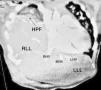

The chosen approach was closure of the defect around the liver, without attempting to separate the fused tissues. The remnant of the diaphragm was stitched to the capsule with horizontal mattress sutures (4−0 polypropylene) and reinforced with polytetrafluoroethylene patches (GORE-TEX®), forming an effective seal to prevent herniation of the bowel loops. After the surgery, the dome of the liver was at the level of the IV intercostal space, as in diaphragmatic eventration (Fig. 2).